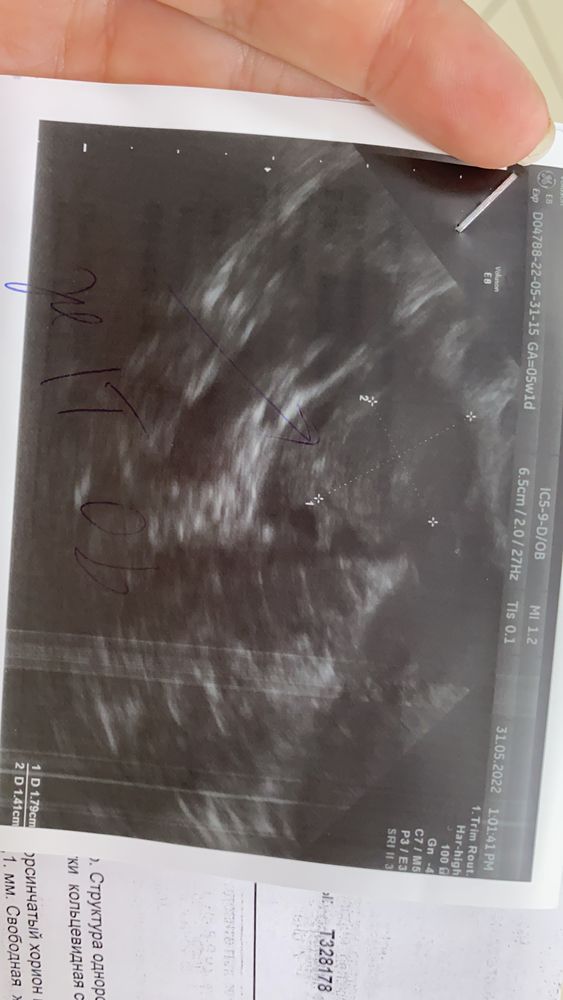

Девочки ,месячные были 25.04-регулярные каждые 28 дней,сделала тест в первый день задержки,беременность,по всем календарям типо 5недель,а сегодня мазня была ,приехала сразу в клинику и вот что написали ,сказали сдать хгч и вообще под большим вопросом беременность развивается или нет 🙈🙈😔

Овуляции скорее всего поздняя,не на 14 д.ц у вас дневнике 4 дня назад очень бледный тест,срок явно меньше